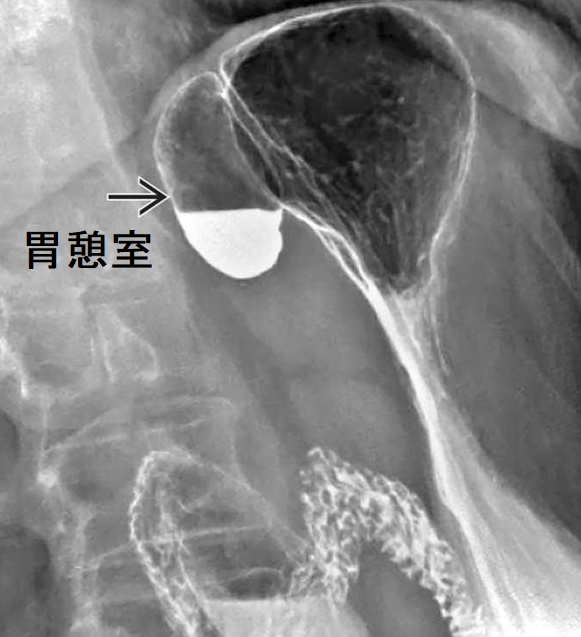

左副腎偶発腫瘍(インシデンタローマ)に見えても、実は胃憩室(gastric diverticulum)の事があります。胃憩室は、胃壁の一部が袋状に拡張し、突出したものです。他の消化管憩室に比べて頻度が低く、甲状腺専門医が遭遇する機会は、ほとんどありません。(表;Qlifeより)

胃憩室は胃穹窿部に好発し、CTにおいて

- 左副腎近傍に位置する

- 内部は胃液なので低吸収(CT値が10HU未満)→左副腎腺腫と鑑別

- 内部にガスを含んでいるか、胃との連続性を確認できれば診断は容易

確定診断として、胃内視鏡もしくは上部消化管造影における憩室(バリウムの貯留)の確認